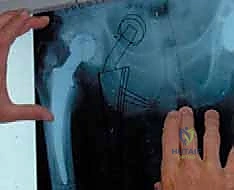

* التصوير الشعاعي: الأشعة السينية (X-rays) لملاحظة أي تخلخل في المفصل أو تآكل في العظام. في حالات معقدة، قد يتم استخدام الأشعة المقطعية (CT scan) أو الرنين المغناطيسي (MRI) المتوافق مع المعادن.

- تشكيل ووضع المباعد الأسمنتي (Antibiotic-Loaded Cement Spacer): بعد التأكد من نظافة الحقل الجراحي، يقوم الجراح بخلط "أسمنت عظمي" طبي مع جرعات عالية جداً من المضادات الحيوية (يتم اختيارها بناءً على المزرعة البكتيرية السابقة).

* المباعد المتحرك (Articulating Spacer): يشبه المفصل الحقيقي ويسمح ببعض الحركة، وهو المفضل لدى الدكتور هطيف متى ما سمحت حالة العظام بذلك، لأنه يسهل إعادة التأهيل لاحقاً.